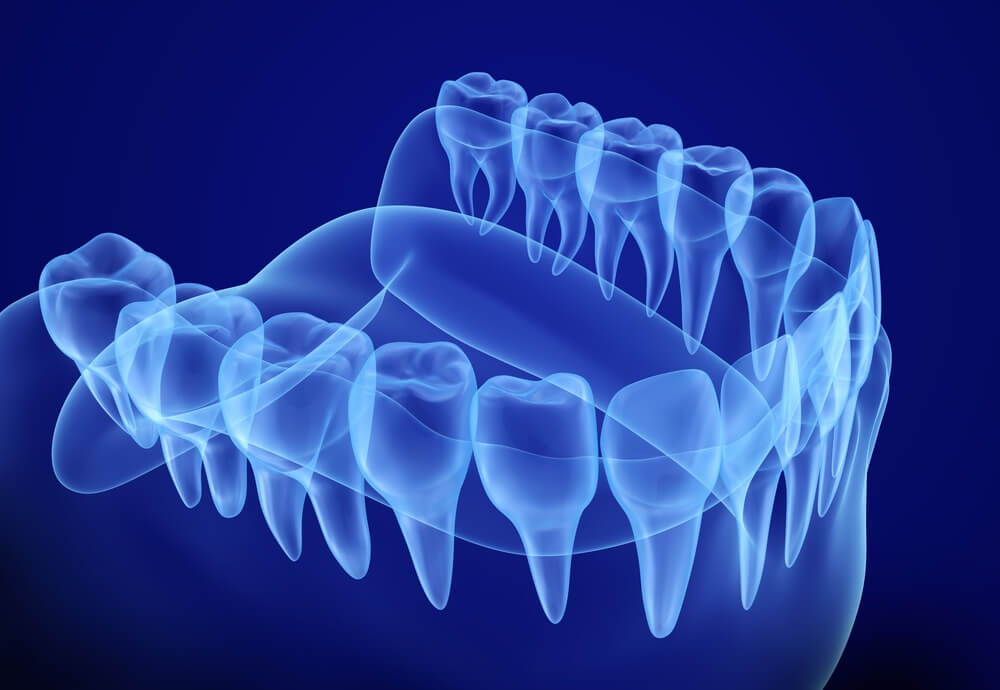

3D dental scan is a revolutionary advancement in modern dentistry, transforming the way dental professionals diagnose, plan, and treat a wide range of dental issues with unparalleled precision and efficiency. Gone are the days of traditional 2D X-rays that only offer limited views of your dental health. With 3D scanning, dentists can now see your entire mouth and jaw in incredible detail, allowing for more accurate diagnoses, personalized treatment plans, and faster results.

Defining what is 3D dental scan

A 3D dental imaging is a cutting-edge technological advancement that allows your dentist to take a detailed, three-dimensional image of your teeth, gums, and jaw. Unlike traditional X-rays, this method doesn’t require the use of any special glasses. By capturing high-resolution images, a 3D scan gives your dentist a more accurate view of what’s happening beneath the surface, helping them diagnose and plan treatments with greater precision.

How does 3D scanning work?

- You will need to sit or stand under the cone beam scanner. Your chin is placed on a special platform to help keep your head still, and a small brace or strap may be used for added stability.

- The scanner will rotate around your head, taking many pictures from various angles.

- The scanner uses a focused X-ray beam to capture detailed images of your mouth and surrounding structures, providing a comprehensive view of your entire oral cavity and even the surrounding facial structures.

- As the scanner rotates and captures the images, the data is processed by specialized software to create a 3D digital image instantly. These pictures will appear on a screen, allowing your dentist to review them right away.

- The 3D scan allows your dentist to examine your oral structures from every angle, making it easier to detect different issues. It also helps in creating detailed and personalized treatment plans.